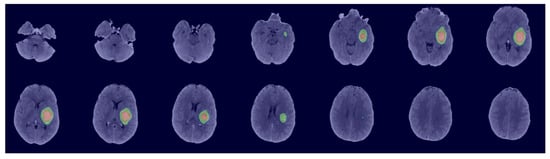

3.1. Model Performance

3.2. Detection of Uncertainty in Segmentation